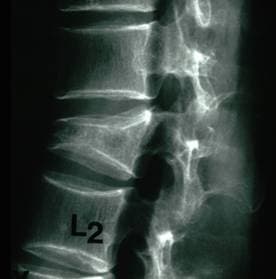

На представлених зображеннях наводиться приклад виконання вертебропластики у хворого з патологічним переломом поперекового хребця внаслідок остеопорозу. На вихідній рентгенограмі видно компресійний перелом хребця, а на правому нижньому знімку в зруйнований хребець введено цемент (біла пляма), який частково відновив висоту хребця.

До вертебропластики

Компресійний перелом поперекового хребця внаслідок остеопорозу